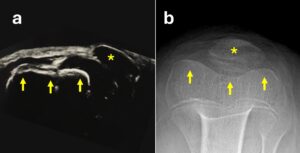

La rotula nei primi anni di vita non è ossificata, per cui nemmeno l’esame radiografico può del tutto aiutare a porre diagnosi.

Per un’esatta diagnosi, è necessario un corretto esame clinico associato a un’ecografia eseguita da mani esperte